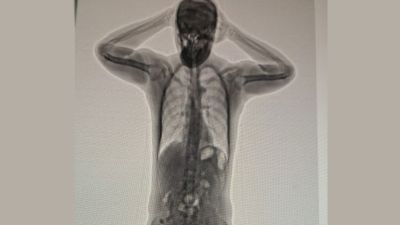

An expat was arrested for attempting to smuggle 50 capsules of heroin inside his body, the Royal Oman Police has announced.

According to the Royal Oman Police, “An Asian national was arrested on charges of possessing narcotic drugs for the purpose of trafficking. More than 50 capsules of heroin were found inside him.”